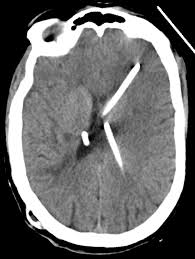

Postoperative Ct Scan Of The Patient Axial View Showing Placement Of Download Scientific Diagram

Non Contrast Ct Scan Of Head Showing Evd In Situ A Followed By Right Download Scientific Diagram

A Postoperative Computed Tomography Ct Scan Of The Initial Download Scientific Diagram